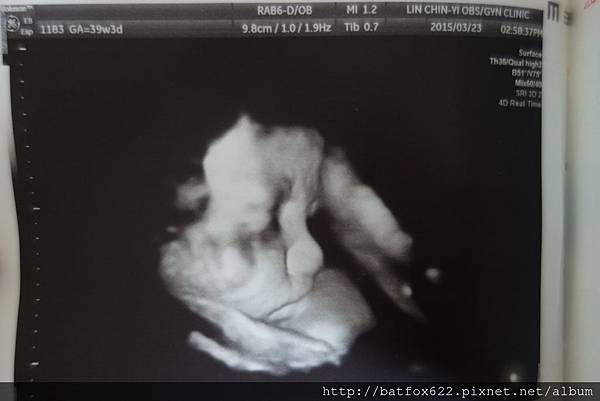

邁入39W~我天天注意胎動的狀況

超過健保給付的十次產檢機會~~我來到第十一次產檢囉~~

自從上次產檢發現胎為轉正,可以自然產之後

這禮拜,寶寶已經滿38W,我隨時都在等待產兆的出現